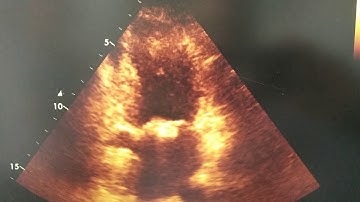

Mitral Annulus Calcification (MAC) & Caseous MAC